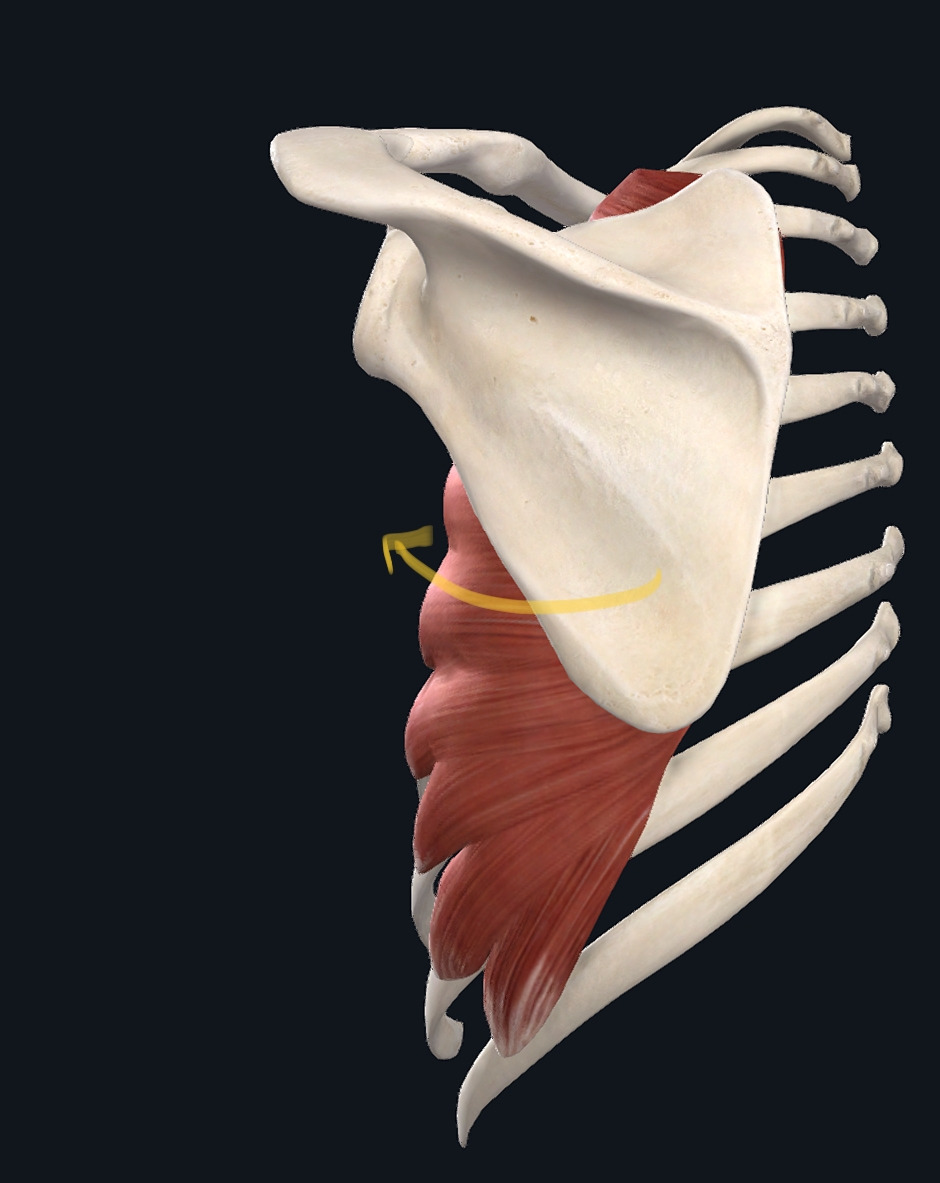

2. 앞톱니근(전거근)

왼쪽이 돌림근띠(1,2,3,어깨밑근은 어깨뼈에 가려짐), 우측이 앞톱니근

어깨치료에 있어 빠질 수 없는 중요한 근육은 어깨돌림근띠(회선근개)이다. 어깨돌림근띠는 어깨뼈에서 위팔뼈 머리 쪽에 부착된 4개의 근육을 총칭한 것인데, 어깨돌림근띠는 위팔뼈 머리가 어깨뼈의 관절면에 제자리 잡도록 도와주는 역할을 하는 근육이다. 실험에 따르면 손에 25파운드(약 11.3kg) 무거운 가방을 들었을 때 어깨돌림근띠의 작용만으로도 이 동작을 수행할 수 있었다고 하니 이 근육의 평상시 작용 능력이 놀라울 따름이다. 어깨 주변의 큰 근육들은(어깨세모근, 위팔두갈래근, 위팔세갈래근)은 근전도(EMG, electromyo graphy) 상 변화가 나타나지 않았다고 한다.4,5 어깨돌림근띠의 강화는 팔을 쉬거나 움직일 때 관절면의 제 위치에 위치하도록 도와줄 것이다. 앞톱니근은 어깨뼈를 위쪽 돌림(화살표 방향)시켜주는 역할을 한다. 어깨뼈의 위쪽 돌림은 팔을 끝까지 드는데 필수적으로 동작이다. 봉우리빗장 관절의 손상은 팔의 움직임 끝에서 주로 통증을 야기시키므로 어깨뼈 위쪽 돌림에 도움을 제공하는 앞톱니근의 강화는 팔 동작의 개선과 통증 감소에 효과적 방법이다. 간략한 운동 방법은 다음과 같다.